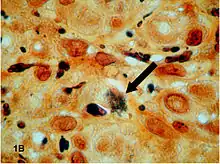

Clusters of bacteria (arrow) shown on Warthin–Starry stain.

Warthin–Starry stains organisms dark brown to black, and the background light golden brown/golden yellow.[5]